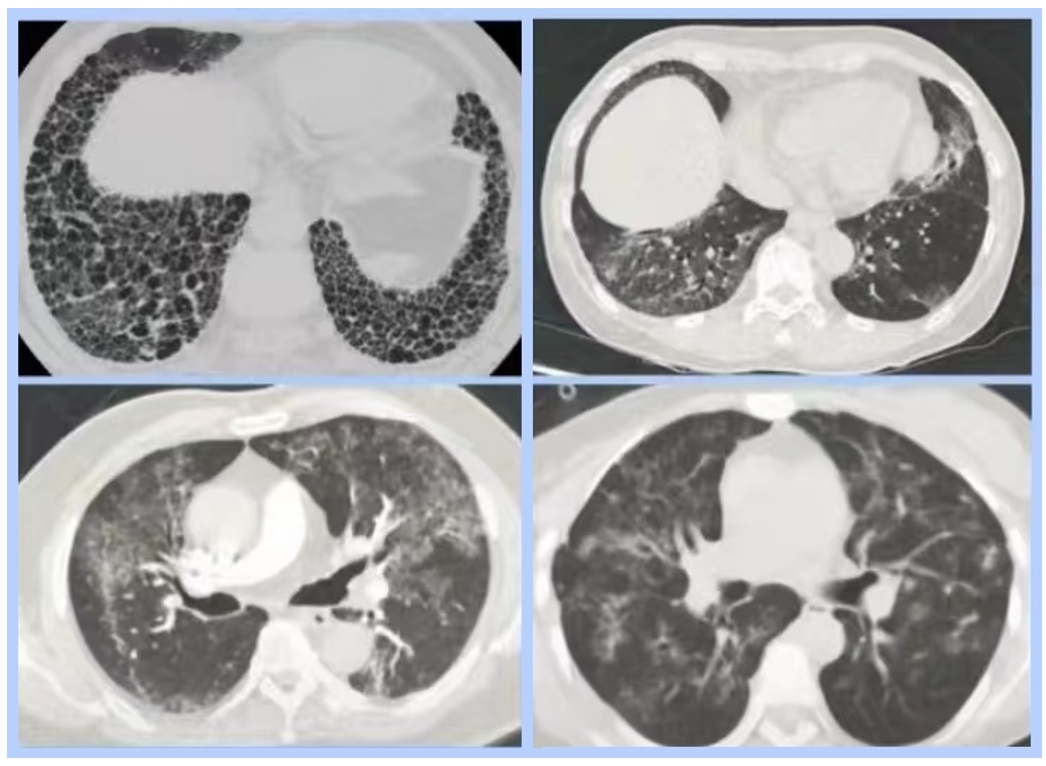

呼吸与危重症医学部结合胸科疾病诊治的难点与问题进行布局,在间质性肺疾病领域,学部在特发性肺纤维化、结缔组织疾病相关间质性肺疾病、结节病、机化性肺炎、过敏性肺炎、药物相关ILD、肺轻链沉积病、肺含铁血黄素沉着症、肺泡蛋白沉着症、肺囊性病变、少见病和不能分类的间质性肺疾病诊疗方面有着丰富的经验,病开展了大量深入研究,形成独有的特色。